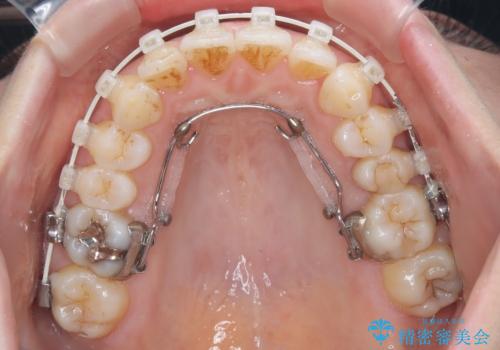

審美装置を用いたワイヤー矯正|非抜歯で歯の凸凹を改善

- 患者様は**歯の凸凹(叢生)**を気にされて来院されました。診査の結果、歯列のスペースが不足しているものの、抜歯をせずに改善できる状態でした。そこで、目立ちにくい審美装置(白いブラケットとホワイトワイヤー)を使用したワイヤー矯正を提案しました。歯列のアーチを広げながら、適宜IPR(歯の幅をわずかに調整する処置)を行い、非抜歯で自然な歯並びへと導く計画を立てました。

治療では、白いブラケットとホワイトワイヤーを使用し、矯正装置が目立ちにくいよう配慮しました。歯列を拡大しながら適切に歯を移動させ、IPRを併用することで、無理なくスペースを確保しました。見た目に配慮しながら、歯の凸凹をスムーズに整え、噛み合わせも改善。患者様からは「装置が思ったより目立たず、歯並びがきれいになって嬉しい」との声をいただきました。